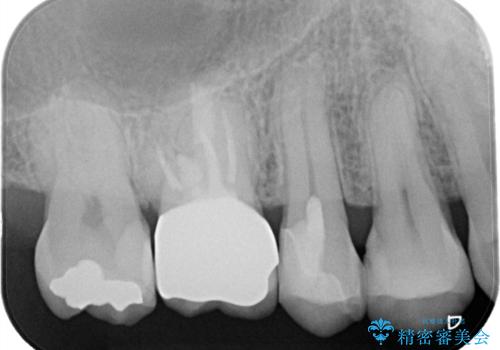

【MTAを用いた生活歯髄療法】神経に到達する深い虫歯

- 以前入れていた、詰め物が取れたことを主訴に来院されました。

虫歯が深く、神経の部屋まで達していました。

術前の検査から、神経が保存できる可能性が高いため部分的断髄法を選択し治療を行いセラミックインレーにて修復しました。

褐色の歯質を認めますが、テトラサイクリンによる変色のためカリエスの残存はありません。